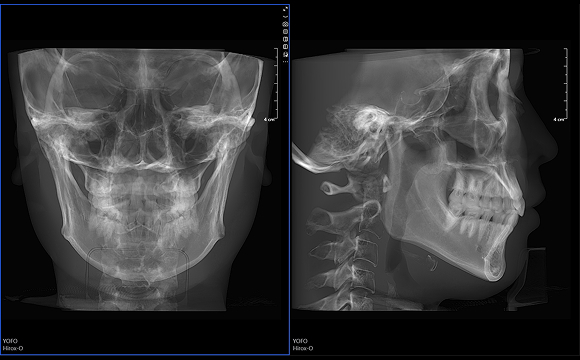

只需一次单圈扫描即可获得CT、3D全景和3D正/侧位影像,并能同时生成3D TMJ视图

提高诊疗效率,避免过度检查,减少患者所受的辐射

• 3D 正侧位

3D 正侧位